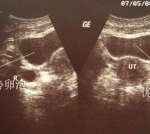

1、协和医院目前有开展人工授精、体外授精-胚胎移植(试管婴儿)、卵细胞浆内单精子注射、冷冻胚胎移植、人工孵化等。医院早在2005年后,试管移植成功率就非常高了,2006年试管成功率直接升至60%。在2010年时,最高试管成功率还在62.1%,到2013年仅一年的时间,其新鲜周期移植成功率高达51.5%,冷藏周期移植成功率就在73.5%,并一直平稳保持在我国内领先地位。

协和医院生殖中心根据每位不育患者的具体情况制定切实可行的治疗方案,近年来不论是新鲜周期移植还是胚胎复苏周期移植都取得了相当满意的妊娠率。

根据北京协和医院官方发布的《协会妇产科辅助生殖中心临床妊娠率国际领先》中有明确写出,该院生殖医学中心冷藏周期时间临床医学怀孕率达73.5%,早已处于国际性领先地位。目前协和医院冷冻胚胎移植技术基本上是没有其他医院可以与其媲美的,患者身体情况较好的,甚至可以达到80%左右的怀孕率。在国内试管行业中协和早已成为了冷冻胚胎移植技术方面的领头羊,所以做冻胚移植选协和能很大程度保证成功率。